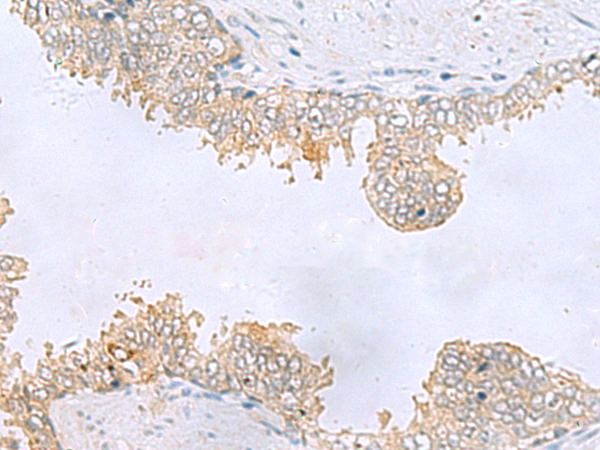

分类: 科研抗体货号: P10213别名: LGP2; RLR-3; D11LGP2; D11lgp2e应用: WB,IHC反应种属: Human, Rat